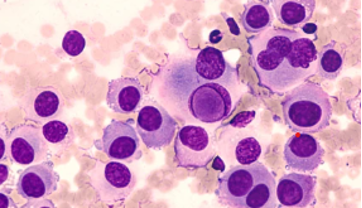

CYTOPATHOLOGY

Figs 1 and 2 from a mass in the right hypochondriac region.

Make your diagnosis.

Fig 1 : Giemsa x 100

Fig 2 : Giemsa x 400